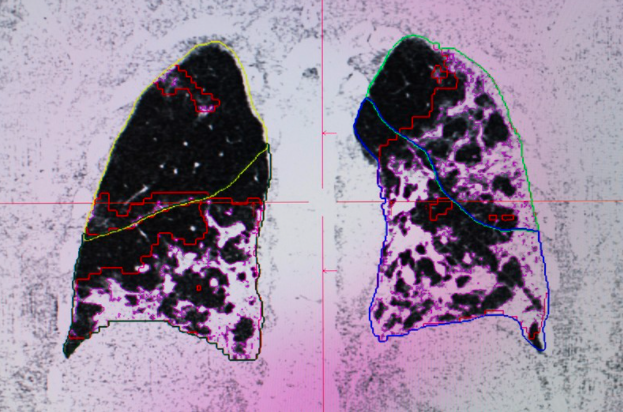

還有醫生將新冠肺炎患者與吸煙者、健康人的胸部X光片(以下簡稱,胸片)圖像對比。

發現新冠肺炎患者的胸片更加“白色混濁”,這種損傷比“老煙槍”更嚴重!

現有臨床報告顯示,新冠病毒一旦造成肺部損傷,約50%—80%的患者胸片可出現“毛玻璃樣混濁”。

640?wx_fmt=png(巴黎一家醫院,給患者做肺部的掃描發現已經嚴重損壞,圖源:Nature)

所以新冠肺炎一旦發展爲重症,將給身體帶來嚴重不可逆的損傷。